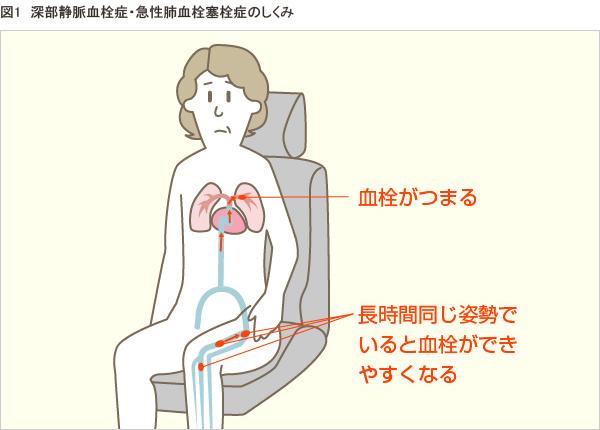

エコノミークラス症候群のイラスト素材29373435- PIXTA。

エコノミークラス症候群広島の調剤薬局 FINE PLUS まえだ薬局・プラス薬局 のブログ。

解剖生理学攻略ページ - この四コマ漫画を見ると ・エコノミー症候群 ・深部静脈血栓症 ・肺塞栓症Facebook。

エコノミークラス症候群病気と治療の検索サイト「メディカルブレイン」。

肺血栓塞栓症・エコノミークラス症候群 男性 のイラスト – フリーイラスト素材集 KuKuKeKe。

エコノミークラス症候群震災時に起こりやすい健康問題と予防法 1看護roo! カンゴルー。

エコノミークラス症候群:入院中に死亡8件 医療事故調査毎日新聞。